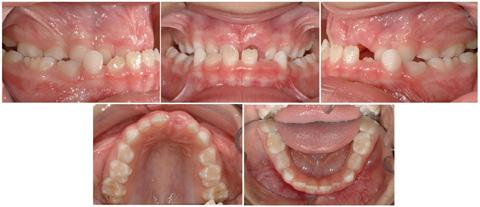

A healthy 6 ½ year girl was referred to me by my orthodontic assistant, a friend of this little girl’s mom. The mother reported no family history of Class III growth, not grandparents, aunts or uncles, or siblings, on either her side or the father’s side. This was perplexing, as it was this patient’s most obvious problem. Orthodontic records were obtained for a thorough understanding of the dental and skeletal characteristics, consideration of potential treatment solutions, and the timing of such treatment.

The INITIAL facial photographs (Figure 1) reveal a mild Class III profile with a hint of mandibular prognathism. The maxilla appears normal. Upon smiling, the mandibular incisors are displayed and hide the maxillary incisors because of the negative overjet and dental deep bite. The midlines are coincident and ‘on’ with the face.

The INITIAL intraoral photographs (Figure 2) show a transverse discrepancy between the maxillary and mandibular posterior teeth. The anteroposterior molar relationship is super Class I. The canine relationship is solid Class I, with space mesial to the mandibular primary canines. Clinical manipulation of the mandible to centric relation placed the primary canines in initial contact, followed by an anterior and vertical functional shift to maximum intercuspation. The overjet between the incisors was negative however, in both centric relation and centric occlusion. Arch length appears adequate in both the maxilla and mandible.